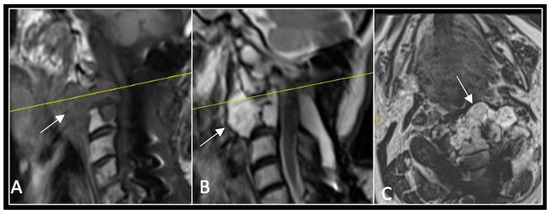

A 73-year-old male presented with an eight-month history of neck pain that was exacerbated on lying flat. He denied any symptoms of myelopathy and radiculopathy. He did not have any constitutional symptoms of malignancy. Past medical history included hypertension, renal cysts, and an ascending thoracic aneurysm. Examination was unremarkable. Diagnostic whole-spine MRI imaging demonstrated a large lobular mass localised to the cervical spine (Figure 2). Biopsy confirmed a conventional chordoma, and he underwent separation surgery followed by adjuvant proton beam therapy. Postoperative surveillance imaging at 12 months demonstrated stable disease (Figure 3).

Figure 2.

MRI demonstrating a destructive lobular lesion localised to the C2 vertebra (chordoma) (arrow). There is significant left-sided extension into the paravertebral tissues laterally and epidural space centrally with indentation of the cord. The yellow line on the sagittal images denotes the level at which the corresponding axial section was obtained. (A) T2-W sagittal; (B) T1W sagittal; (C) T2W axial.